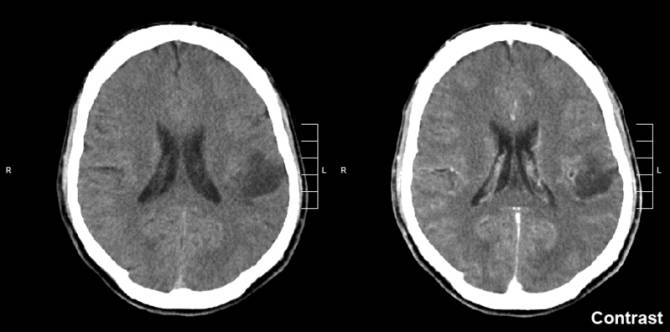

![[Img #48577]](upload/img/periodico/img_48577.jpg)

Glioma. (Foto: Wikimedia Commons)

Nueve días después de la inoculación, observaron que el grupo de animales tratado únicamente con BSO exhibió un aumento 70 veces mayor de tamaño de los tumores en comparación con su volumen inicial.

En tanto, en el grupo de animales tratados sólo con TMZ se registró un aumento aproximadamente 40 veces superior al volumen tumoral, y en el grupo sometido al tratamiento con la combinación de ambos fármacos se verificó una reducción de la progresión tumoral aproximadamente 10 veces mayor durante el período de tiempo de tratamiento.

“Estamos proponiendo el uso de BSO combinado con TMZ para incrementar laeficacia del tratamiento quimioterapéutico de gliomas y melanomas”, dijo Ribeiro Reily Rocha.